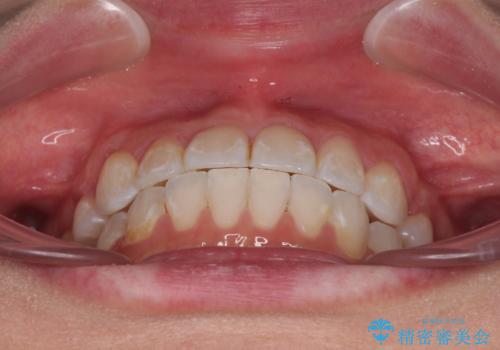

奥歯の咬み合わせを維持しながら正中位置を改善するために、補助装置を使用しました。

予定より期間がかかりましたが、上下の正中位置を綺麗に一致させることができました。